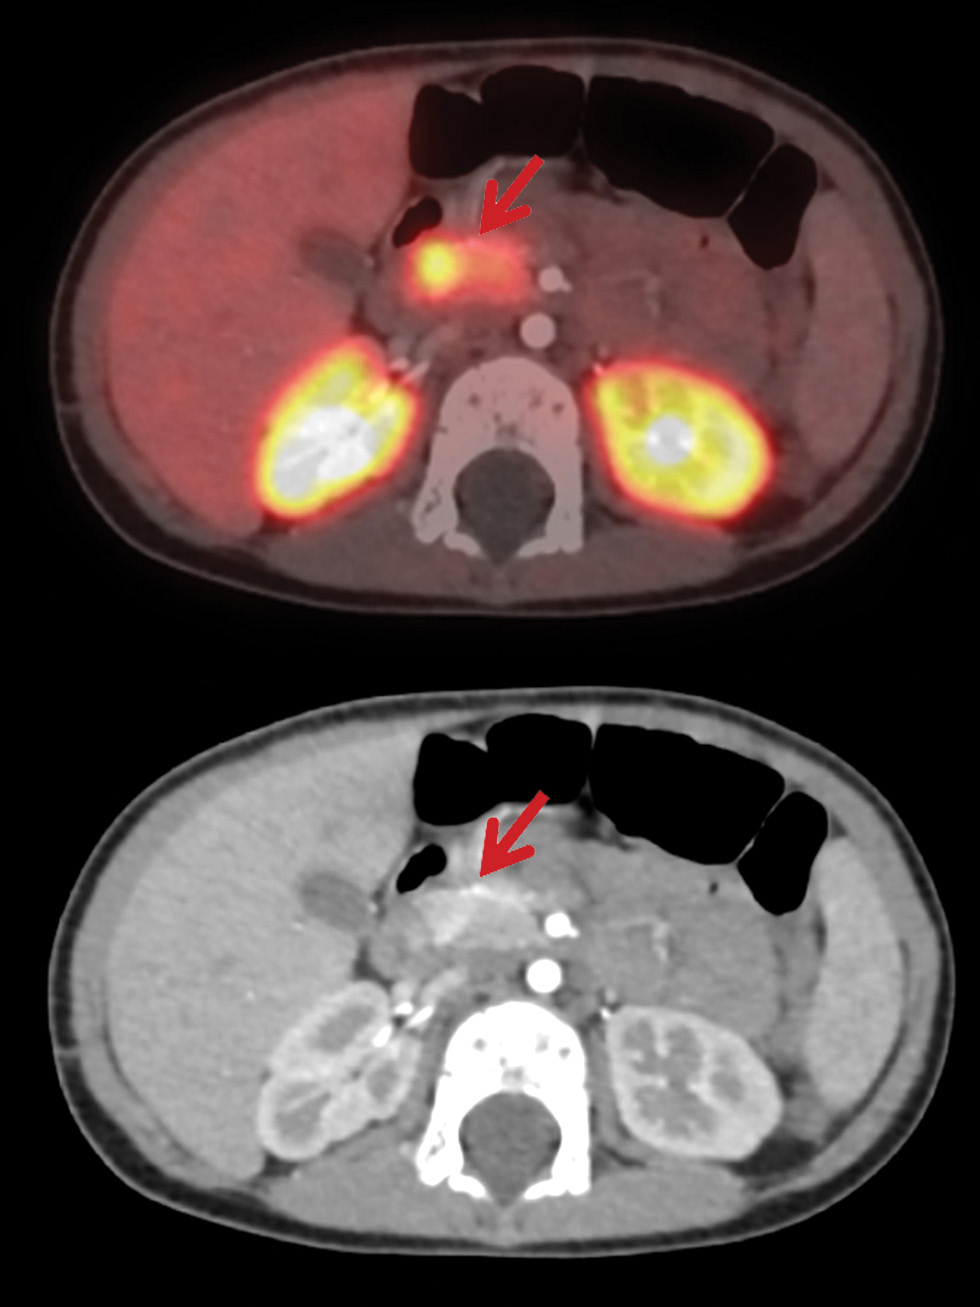

Учитывая принципиальные различия в объеме оперативного вмешательства, пациентам с фармакорезистентным течением ВГИ показано проведение ПЭТ с 18F-ДОФА. Визуализация поджелудочной железы происходит за счет захвата островковыми клетками радиоизотопа [18, 19]. В мировой литературе предлагается применение математического показателя ПИ для оценки результатов ПЭТ. При значении ПИ более 1,5 устанавливается фокальная форма, при значении ПИ менее 1,3 диагностируется диффузная форма ВГИ [20]. Однако на практике существуют определенные затруднения при применении данного параметра для дифференциальной диагностики морфологических форм. В нашем исследовании, несмотря на гистологически подтвержденную фокальную форму, у 1/3 пациентов значение ПИ было менее 1,5. Фокальная форма ВГИ по результатам ПЭТ у данной группы пациентов была предположена исходя из визуальных данных (рис. 3). Значение ПИ было максимальным в промежутках через 20–60 мин после введения радиоизотопа. Таким образом, вызывает сомнения необходимость проведения сканирования через 10 мин после исследования. Затруднения в применении ПИ могут возникнуть за счет физиологического повышенного захвата 18F-ДОФА в области головки поджелудочной железы, при оценке гигантских фокусов или мультифокусов [21, 22].

Рис. 3. Результаты ПЭТ/КТ с 18F-ДОФА у пациентов с различными морфологическими формами ВГИ.

а – диффузная форма ВГИ. Захват 18F-ДОФА равномерен; б – фокальная форма ВГИ. Визуализируется очаг накопления радиофармпрепарата; в – эктопическая локализация фокальной формы ВГИ. Очаг накопления радиоизотопа визуализируется в области двенадцатиперстной кишки.